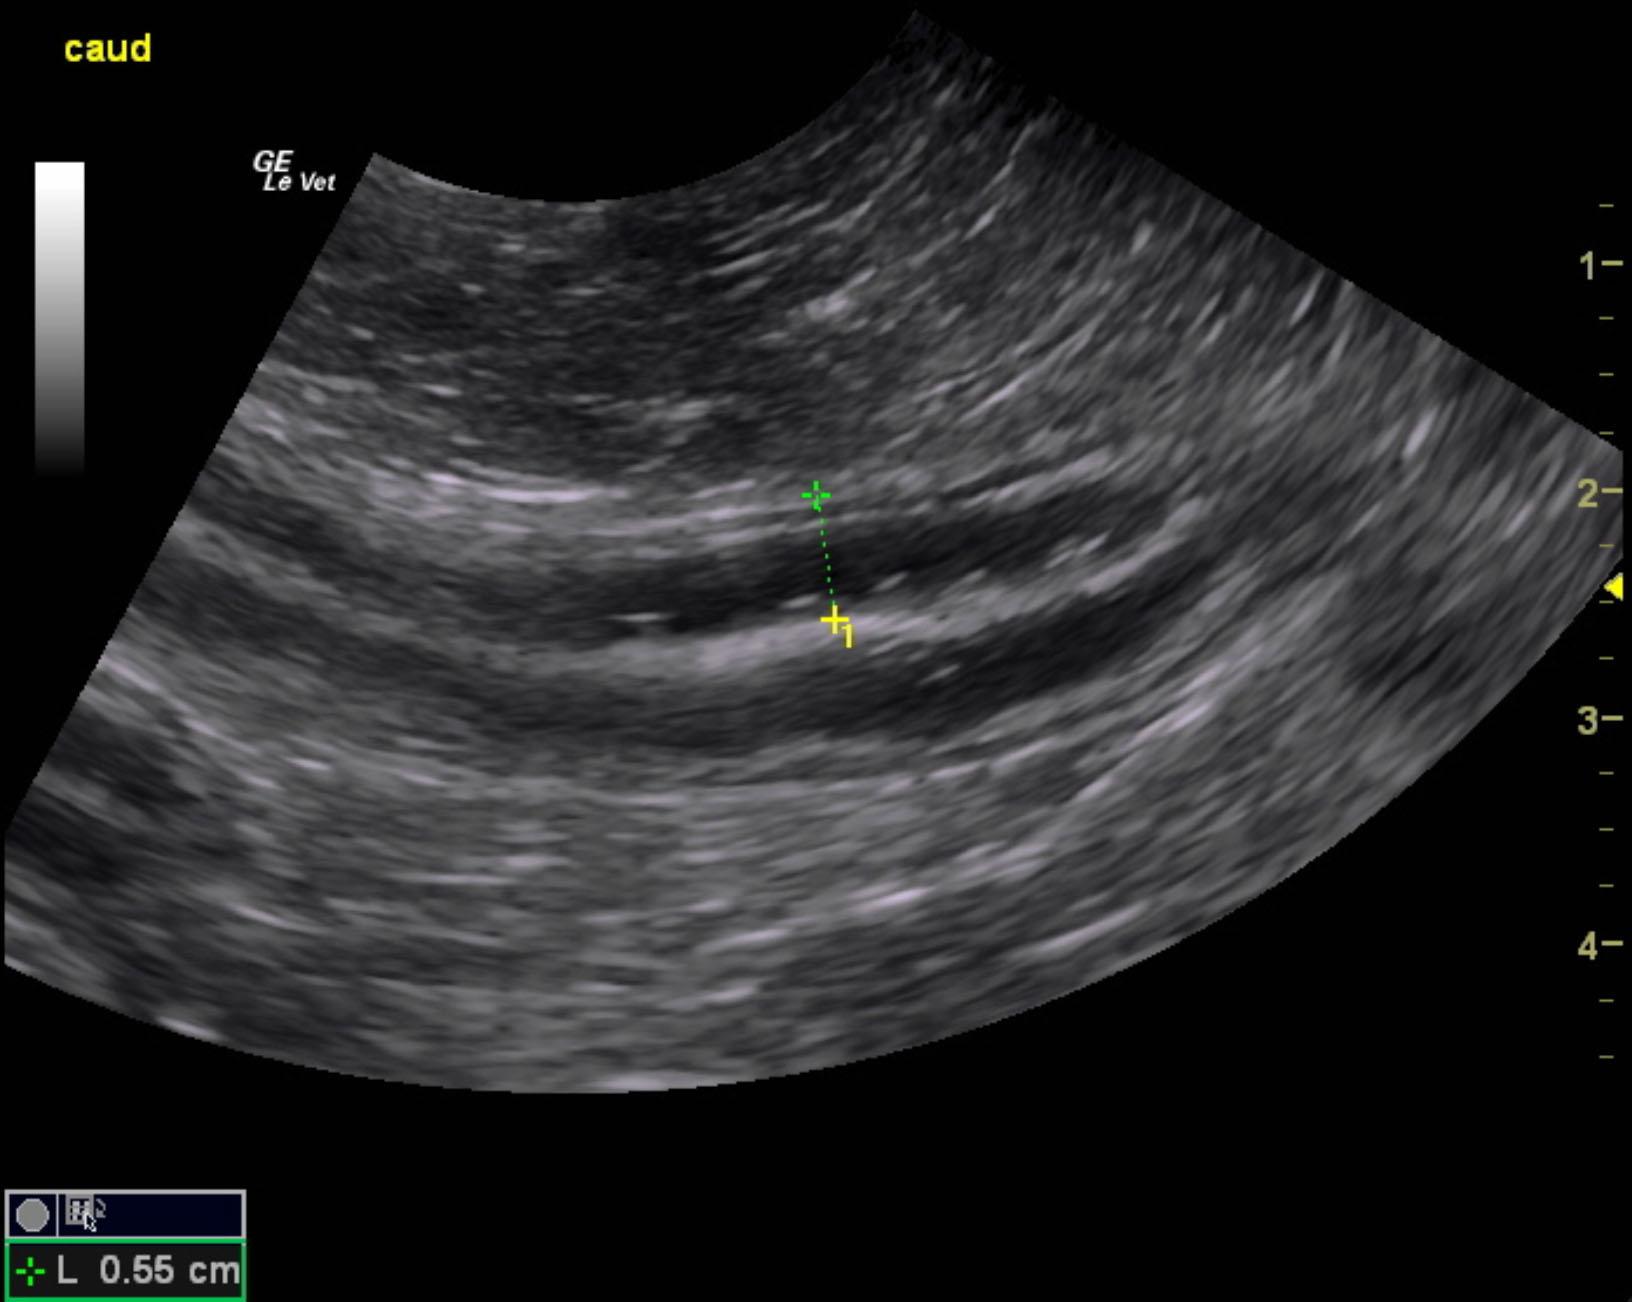

The patient is a canine Rottweiler, NM, 10 years, 105.8 lbs. who was presented for weight loss, occasional v/d, history of eating rugs/carpets and dog beds on multiple occasions, however this is a new behavior change. No vomiting currently. Urine specific gravity 1.025, pH 6.5.